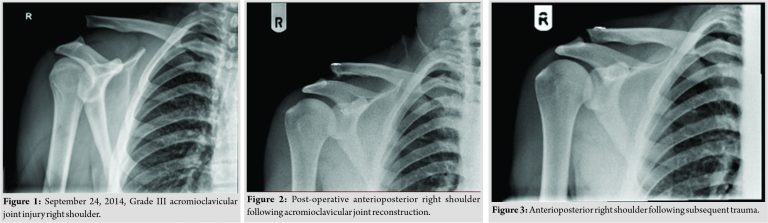

A fit and healthy 28-year-old right hand dominant patient presented with bilateral symptoms of shoulder instability after multiple impacts while playing rugby. The right shoulder clinically demonstrated greater anteroposterior laxity than the left and was more symptomatic. Symptoms included intermittent mechanical symptoms of “’catching”’ within the shoulder. There was also evidence of scarring consistent with a previous ACJ reconstruction. Clinically, there had been partial failure of the reconstruction with subluxation at the ACJ. There was no other relevant history of note. On reviewing the patients records, it appeared that the patient had a prior history of ACJ separation, a result of a rugby injury 4 years previously. He had suffered a high Grade III ACJ separation of the right shoulder. This was reconstructed within 2 weeks of the injury using a standard arthroscopic technique using two dog bone buttons and two FiberTape sutures. The patient had an uncomplicated recovery and a post-operative X-ray demonstrated a good reduction and button positions. (Fig. 2). Three years after this initial presentation, the patient had sustained a further rugby injury to the right shoulder. Examination revealed partial failure of the reconstruction. X-rays demonstrated minimal ACJ displacement and button displacement and it was, therefore, decided to manage the patient conservatively (Fig. 3). The patient returned to unrestricted sport.